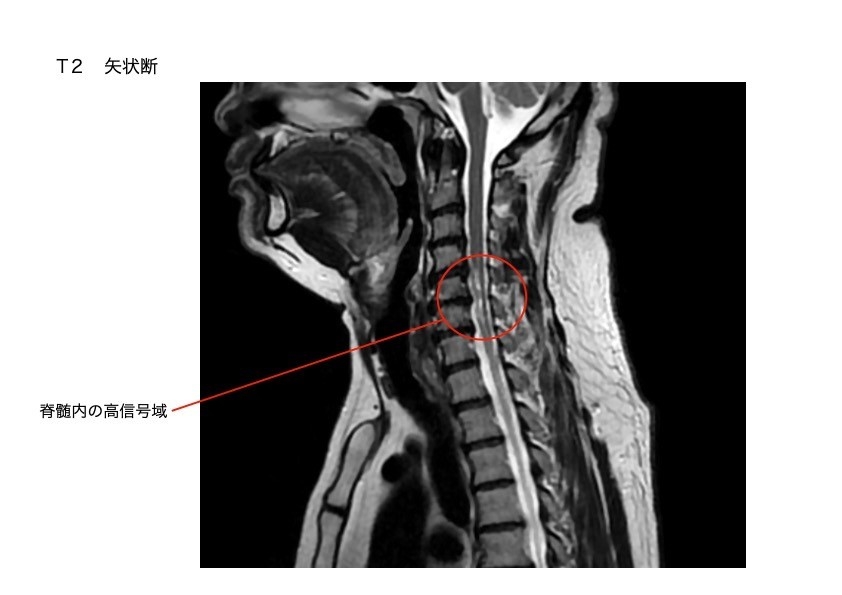

・脊髄梗塞 (前脊髄動脈症候群)

前脊髄動脈の支配領域である脊髄腹側約2/3錐体路と脊髄視床路に血流障害が生じます。

脊髄の中の動脈が血栓で詰まり、首から下の脊髄神経が壊死しました。